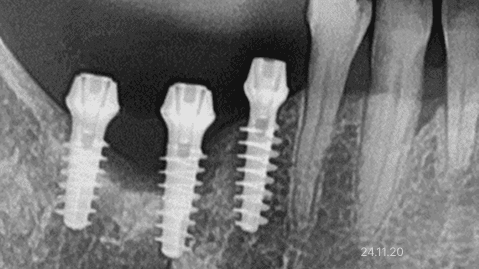

뼈이식 · 전체 임플란트

잇몸뼈 부족 · 타 치과 임플란트 불가판정 · 장기간 틀니 사용

*위 사진은 환자 본인 동의를 얻어 동일 조건에서 촬영 되었습니다. 모든 치료에는 부작용이 발생할 수가 있습니다.